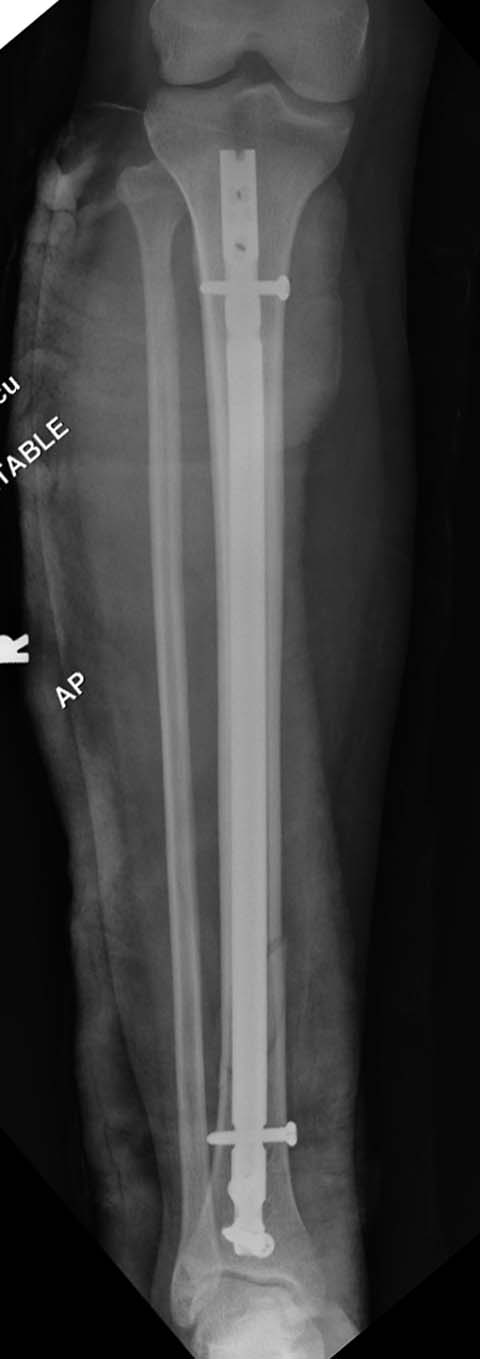

Разбор любого случая кому-то поможет лучше ориентироваться в решении вопросов, потому что в нашей работе встречаются разные связанные и несвязанные с мастерством хирурга ситуации. Возможно, отсутствие полного набора гвоздей повлияло на выбор короткого имплантата, имеется угловая и ротационная деформации. Независимо от локализации, стабильность создается, когда гвоздь проксимально не глубже 1.5 см (облегчает удаление) и дистально доходит до epiphyseal scar.

Кроме этого, имеет значение предварительная репозиция и риминг в центре канала. Интактная малоберцовая иногда затрудняет репозицию, но существуют разные приемы, нп. при застарелом можно применить дистракторы: стержневой или кольца Илизарова, а при свежих - перкутанно Weber clamp.

Мнение о том, что гвоздь сделает репозицию не всегда соответствует истине. Снимки показывают на неудачную попытку исправить направление гвоздя с помощью “поллеров”. Прием возможен только тогда, когда проход риминга в центре канала, иначе толкать гвоздь некуда.

Здесь несколько снимков изолированного перелома большеберцовой с интактной малоберцовой. Weber clamp, блокирующие спицы и риминг в центре канала отрепонировал перелом....

В нашем распоряжении были все размеры гвоздей, но взяли этот.

Следующий размер на 15 мм больше и доходил до уровня сустава. Иногда даже самая идеальная фиксация не гарантирует сращение, надо оставить запас для динамизации. Дистально исчерпан лимит, а проксимально достаточно места...